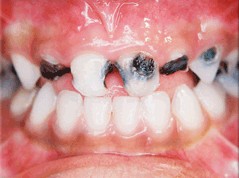

Alle fakta viser, at fluorid ikke har noget med cariesfrihed at gøre. Og cariesfrihed er det vi ønsker for risikopatienterne og alle andre. Netop for risikopatienterne er forskernes forbryderiske udtalelser gift. Når man har set små børn med masser af huller, skrigende af smerter og angst i tandlægestolen; og man ved, at fluor er medvirkende årsag, fordi det får folk til at slække på plakfjernelsen. Så undrer man sig over, at myndighederne tillader, at kvaksalvere, der burde sidde bag tremmer, går frit omkring. At kalde det videnskabelig uredelighed er århundredets underdrivelse.

Med kampagner og anbefalinger om fluor og sukker er der sat spørgsmålstegn ved tandplejens reelle hensigter. Det er kun regelmæssig plakfjernelse der kan give cariesfrihed. Alle andre metoder kan kun medføre en sænket cariesprogressionshastighed. Sålænge der er plak på tænderne vil der være caries. Uden plak er der ingen caries, helt uafhængigt af fluor og sukker. Stadig flere er cariesfrie, en cariesfrihed som helt uden tvivl er opnået ved bedre plakfjernelse. Men der er stadig risikopatienter med caries som har brug for bedre regelmæssig plakfjernelse. Den plak der er årsagen til caries på risikopatienternes tænder, har de netop på grund af den forvirring som kvaksalverne skaber omkring plakfjernelse med sukker og fluor. De har ikke skyggen af bevis for at de cariesfri bruger mindre sukker eller mere fluor. Vi burde for længst have været cariesfrie allesammen. Men sålænge kvaksalverne får lov til at udbrede deres løgne, vil der være ofre der falder for dem. Små børn vil til stadighed komme grædende til tandlægen med huller i tænderne forårsaget af plak der ikke er blevet fjernet på grund af de skadelige fluor- og sukkerkampagner.